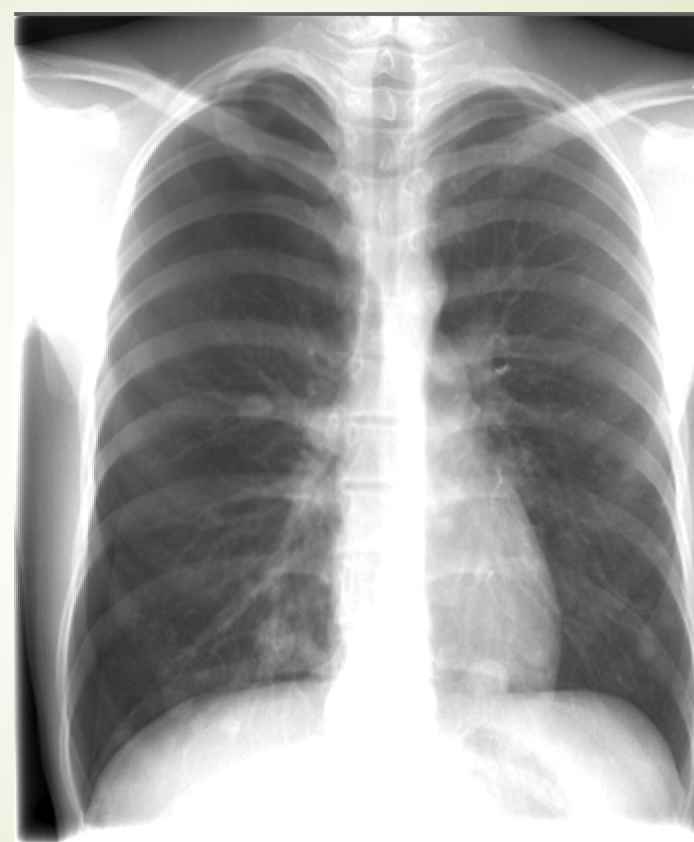

Chest X-ray

which lung has pneumothorax

the right one